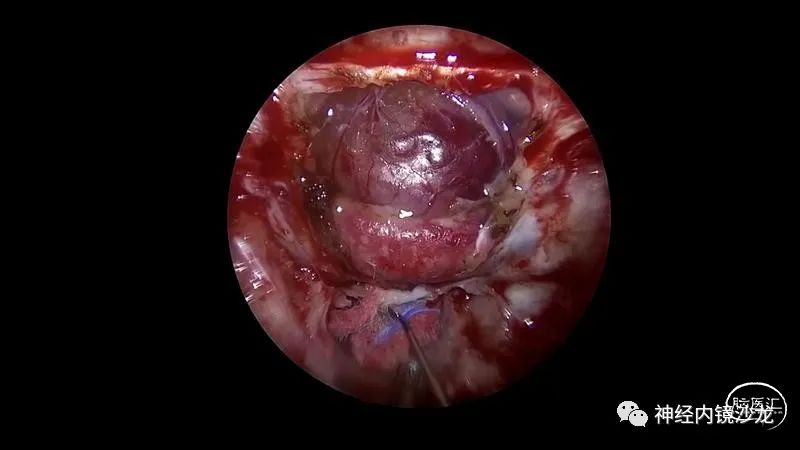

精彩图表

从事神经外科十余年,擅长神经外科肿瘤诊治,尤其是神经内镜微创手术治疗垂体瘤、颅咽管瘤、脑膜瘤等颅底肿瘤